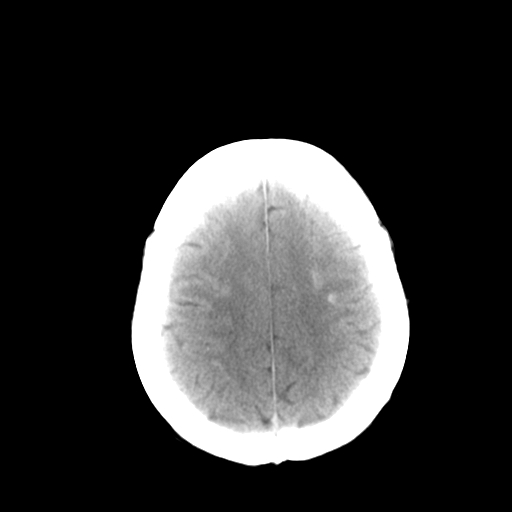

标题: CT13482:对称钙化!外伤就诊! [打印本页]

标题: CT13482:对称钙化!外伤就诊!

女,58 ,对称钙化!外伤就诊!